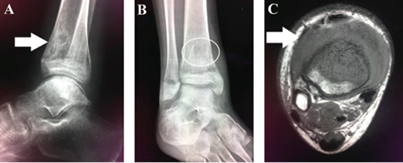

Right ankle radiograph showed a mixed lesion with sclerotic and lytic areas in the anterior aspect of the tibia metaphysis (Figures IA and IB). Right ankle magnetic resonance imaging detected an infiltrative low-signal lesion located in the anterior aspect of the distal tibia metaphysis, with epiphyseal and extraosseous extension, associated joint effusion, and adjacent soft tissue edema (Figure IC).

Figure IA X-ray of the right ankle on lateral view showing a mixed lesion with sclerotic and lytic areas in the anterior aspect of the distal tibia metaphysis (white arrow). Figure IB - X-ray of the right ankle on anteroposterior view showing a mixed lesion with sclerotic and lytic areas in the distal tibia metaphysis (white circle). Figure IC - MRI of the right ankle on axial T1-weighted imaging showings an infiltrative low-signal lesion located in the anterior aspect of the distal tibia metaphysis and extraosseous extension, with adjacent soft tissue edema (white arrow).